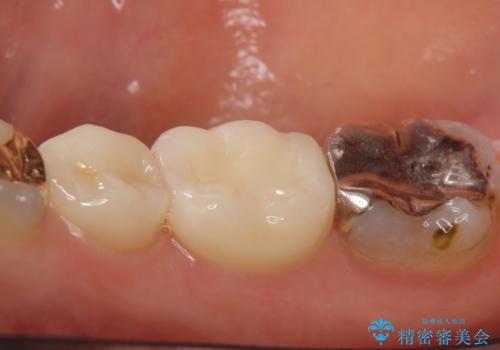

- 右下奥の歯茎がたまに腫れて膿が出るので診て欲しいといらっしゃった方の症例です。

診査の結果右下6の歯の神経が死んでいたため根管治療を行い、オールセラミッククラウンによる補綴を行いました。

今回用いたオールセラミッククラウンはジルコニアフレームという白い素材の上にセラミックを盛っているため、審美性が非常に高いのが特徴です。